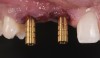

The bone graft underwent a 6-month maturation period to allow integration of the biomaterial. At this point, teeth Nos. 6 and 8 were atraumatically removed, and implants were immediately placed into the extraction sites without elevating a flap (Figure 19 through Figure 21). The gingival tissues exhibited a moderate degree of inflammation as a result of the difficult access for oral hygiene procedures under the post-orthodontic splint, which at the time had remained in place for 9 months. Implants featuring a tapered design were selected, and excellent primary stability was achieved (Figure 22 and Figure 23). Insertion torque values in excess of 45 Ncm were recorded for both implants, which allowed an immediate loading protocol.6,7,63,64

Fig 19. After extraction of teeth Nos. 6 and 8, implants were placed and a screw-retained immediate three-unit provisional was delivered.

Figure 19

Fig 21. After extraction of teeth Nos. 6 and 8, implants were placed and a screw-retained immediate three-unit provisional was delivered.

Figure 21

Fig 22. The implants selected for teeth Nos. 6 (Fig 22) and 8 (Fig 23) featured a tapered design.

Figure 22